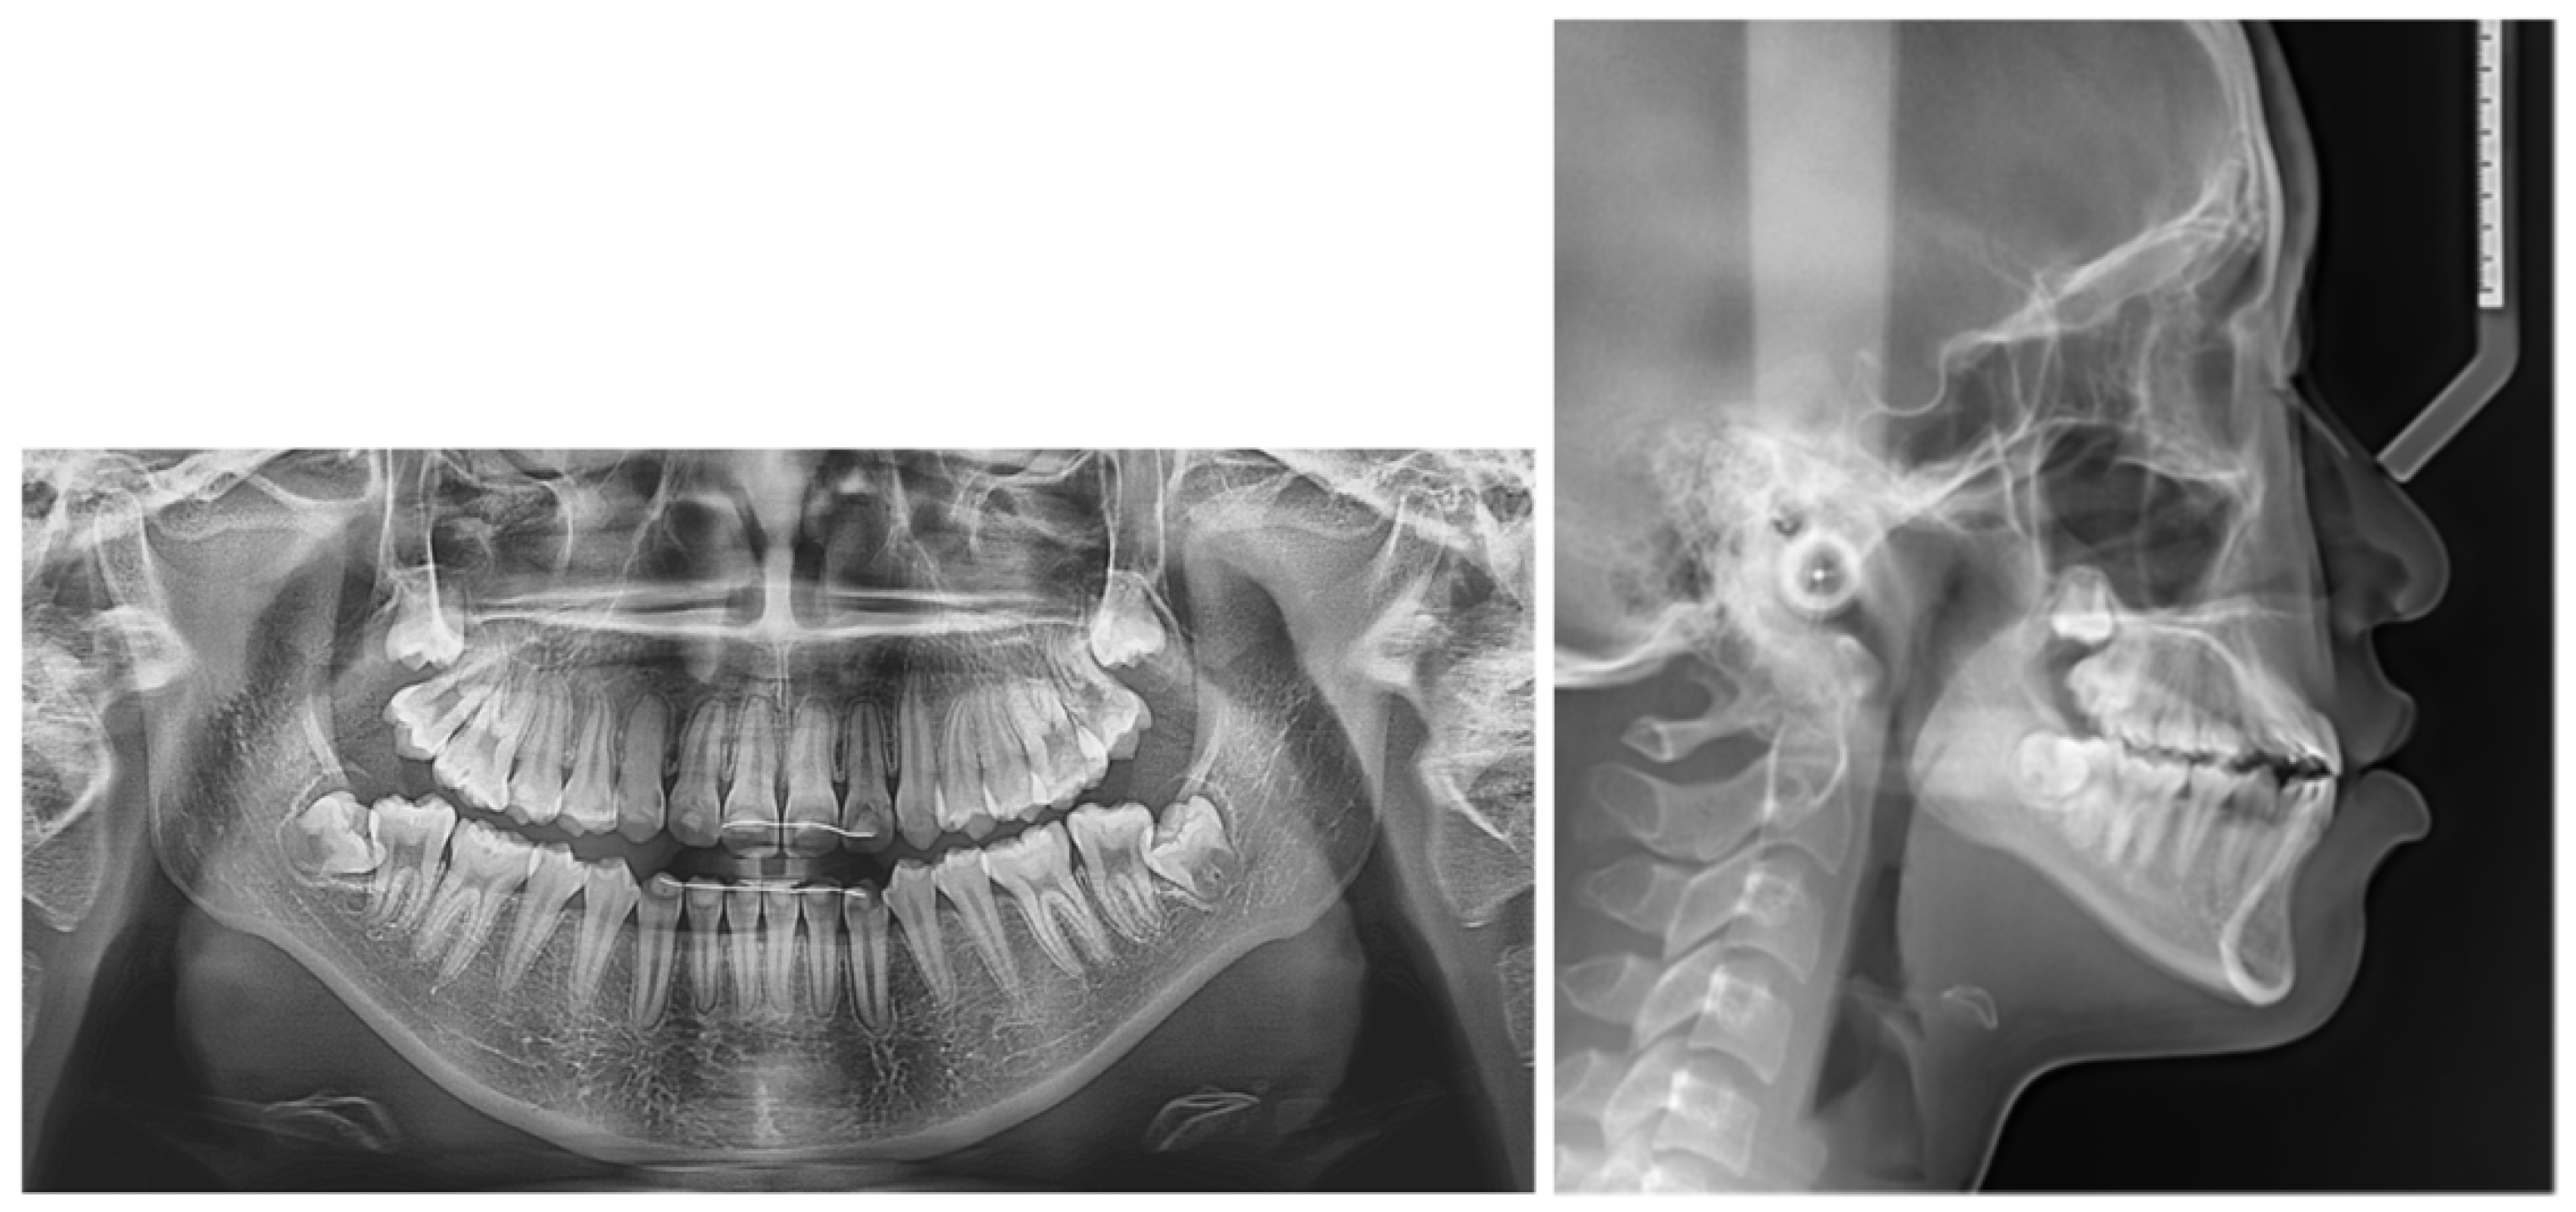

2.5. Treatment Results